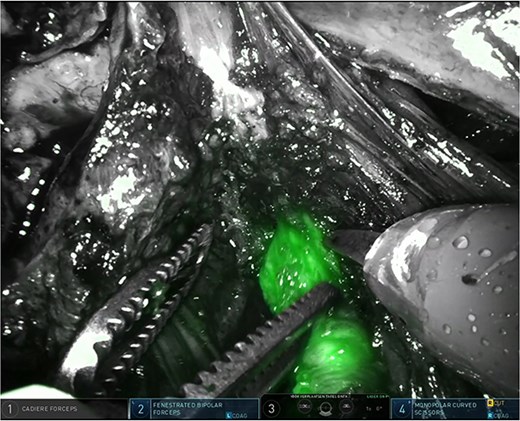

The right pelvic side wall was opened to identify and mobilize the right stenosed ureter along its course in the right pelvic side wall, towards its crossing with the uterine artery. Using intermittent near-infrared fluorescence (NIRF) imaging we could easily identify the right distal ureter, highlighted by ICG (Fig. 2). Ureterolysis was facilitated by the ICG absorption in the ureteral mucosa/wall as visible during the procedure (Supplementary Video; https://youtu.be/oz2k_S9L_Vk). Careful dissection of the fibrotic tissue around the stenosed ureter resulted in release of the ureter and the area where the partial stenosis was present (Fig. 3). The parametrial endometriosis was further dissected and mobilized towards the posterior cervix. Endometriosis was apparently invading the posterior lip of the cervix with several small cysts/cavities filled with dark brown ‘chocolate-like’ endometrial fluid, making clear margins difficult for resection (Supplementary Video; https://youtu.be/oz2k_S9L_Vk). All the cysts/cavities in the posterior cervix were resected and the superficial cervical stroma was coagulated with spray diathermy. The whole endometriosis area was further dissected towards the posterior vaginal wall, with opening the vagina in order to achieve complete resection of the deep endometriosis. At the end of the procedure a prophylactic double-J stent was placed in the right ureter for 3 months to prevent secondary fibrosis/stenosis. The patient was discharged after 48 hrs. The renal function postoperatively was normal. As hormonal therapy she received relugolix combination therapy (relugolix 40 mg, estradiol 1 mg, norethisterone acetate 0·5 mg). An MRI scan four months after surgery showed no evidence of residual or recurrent deep infiltrative endometriosis (Supplementary Video; https://youtu.be/oz2k_S9L_Vk). A clinical visit five and ten months after surgery revealed no significant pain complaints, with normal daily activities. An expert ultrasound scan 10 months after surgery revealed no evidence of recurrent deep endometriosis.

Easy identification of the surgical margins between the connective tissue in the parametrium and the distal ureter using ICG.

Partially stenosed and medially distorted ureter visualized by ICG and NIRF.